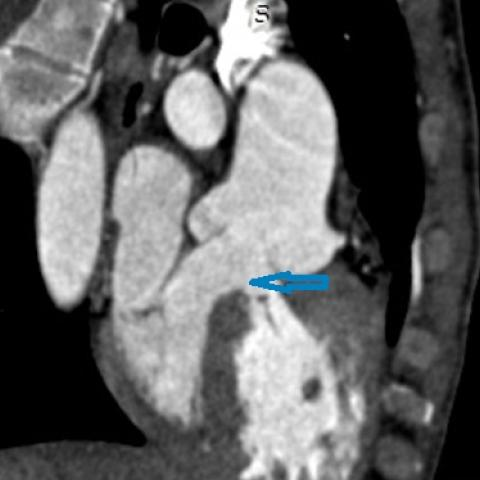

Clinical Case [Uncaptioned image] [Uncaptioned image]

Image Findings: The patient underwent contrast-enhanced computed tomography which showed features of a congested liver with flip-flop pattern of enhancement. Hepatic veins show hypoattenuation on delayed phase. An accessory hepatic vein is also noted in segment VI. A diagnosis of Budd Chiari syndrome (BCS) was made on the basis of the clinical and imaging features. The patient was referred to the interventional radiology team for an endovascular rescue. On conventional venogram, the diagnosis of BCS was confirmed as the hepatic veins were thrombosed. An accessory segment VI hepatic vein was noted draining into the IVC…

Title: Accessory right inferior hepatic vein [Uncaptioned image] [Uncaptioned image]

Discussion:Marked dilatation of the pulmonary trunk (6.7 cm) with the right (5.4 cm) and left (4 cm) main branches. Lung window shows mild bilateral diffuse faint groundglass centrilobular lung nodules that may reflect an underlying infection. Scans through the upper abdomen revealed average size cirrhotic liver and reflux of contrast into the IVC and hepatic veins with Incidental opacification of accessory right inferior hepatic vein…